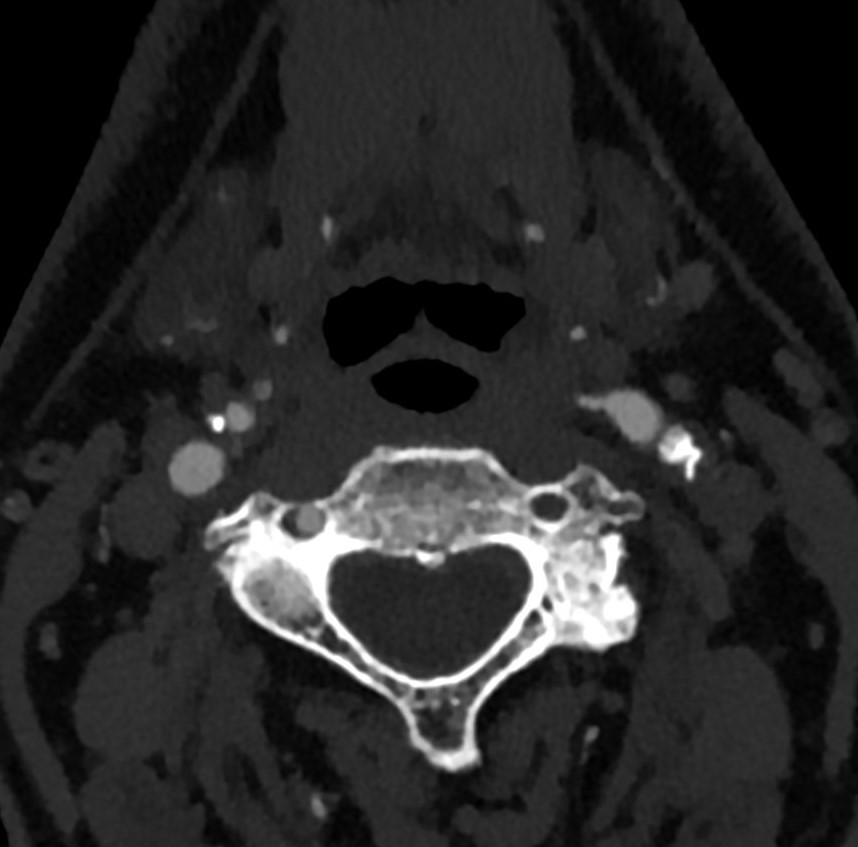

Image

Original axial slice of the CTA

' "Curving" secondary reformatted image following the way of the artery'

Fig. 16., 17. Atherosclerotic plaques in the carotid bifurcation, causing significant stenosis

CTA (if done by multislice - above 64- CT) has the main advantage of showing in detail even highly irregular contoured, unevenly calcified plaques, and the residual lumen so the grade of the stenosis can be measured with more confidence. That is why, nowadays, if there are no contraindications, duplex US is always followed by a CTA, in special cases MRA as an alternative.